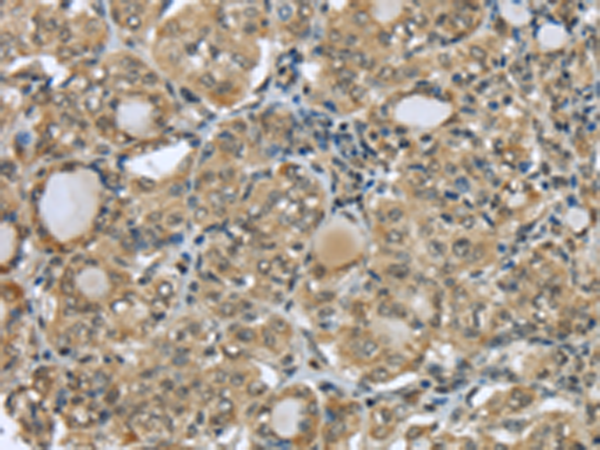

分类: 科研抗体货号: P08927别名: TRP14; TXNL5应用: IHC反应种属: Human, Mouse